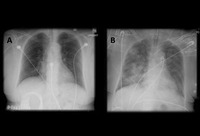

Aspiração aguda

A. Radiografia torácica portátil ortostática antes da aspiração; B. Radiografia torácica 1 hora após a aspiração, mostrando infiltrados alveolares difusos bilaterais, piores nas bases do lado direito

Do acervo de Dr. Henri Colt